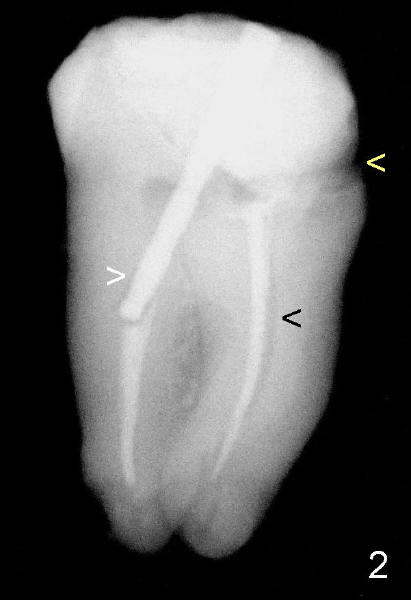

Fig. 1 and 2 show the abutment tooth #32 in vivo and in vitro, respectively. Yellow < in Fig.1,2 point to open margin in the mesiobuccal aspect of the crown/tooth. While the white > in Fig.1 points to unfilled pulpal chamber, the one in Fig.2 shows more clearly the void around the post in the distal canal. Oblique projection shows curved void associated with the mesial canal (Fig.2). RCT failure is complex, both endodontic and restorative (coronal leakage). Return to main text